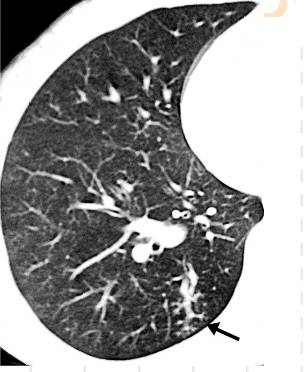

(2)肺结核:TIB在肺结核中较常见,Kashyap等认为树芽征和小叶中心结节是支气管内结核的特征性HRCT表现。

结核,高分辨率CT显示右肺周围边界不清,大小不等,这些征象代表了支气管内结核的播散